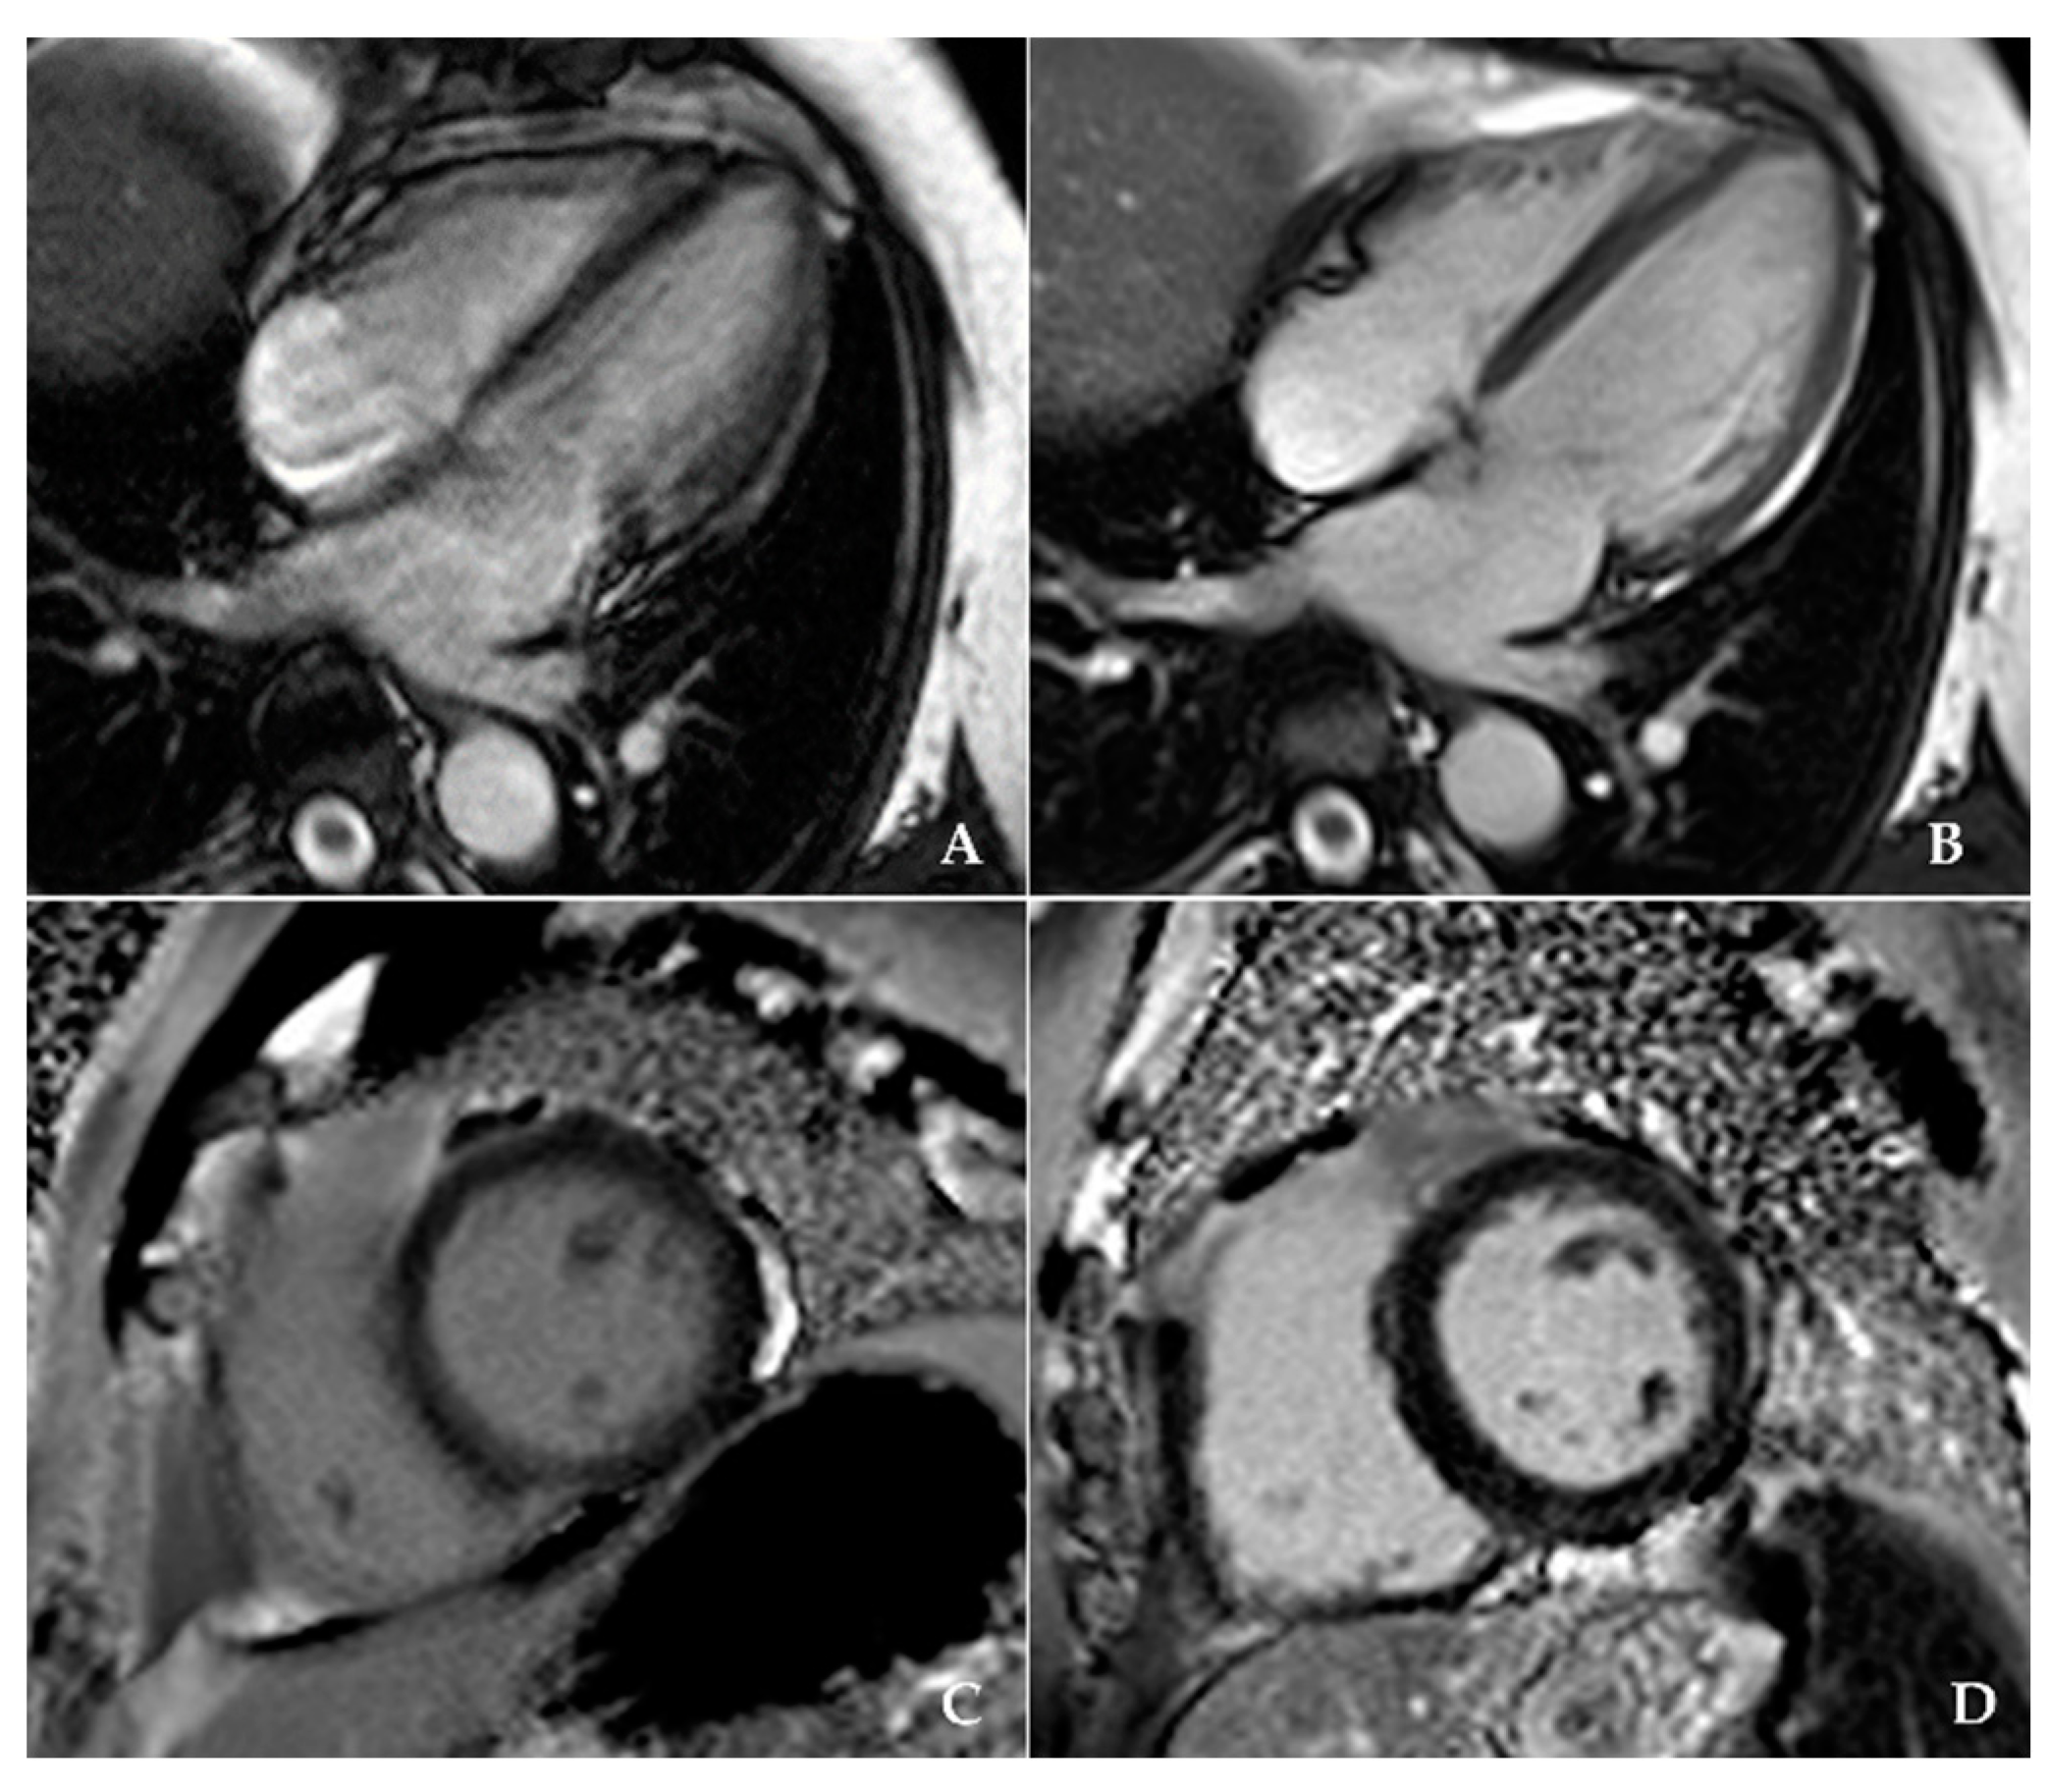

| Image Quality (1 bad, 2 moderate, 3 very good, 4 excellent) | 1.62 ± 0.49 | 3.46 ± 0.51 | <0.001 |